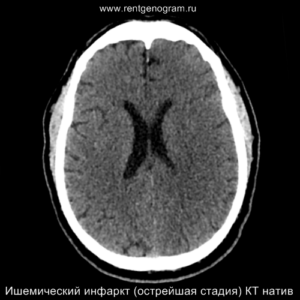

Ишемический инфаркт

Ишемический инфаркт — это повреждение центральной нервной системы, вызванное острым нарушением мозгового кровоснабжения с дальнейшим развитием гипоксии нервной ткани.

Этапы ишемического инфаркта

- острая фаза (первые 6 часов – возможны вмешательства)

- острое течение (с 6 до 24 часов – инфаркт виден на КТ и МРТ)

- подострая фаза (с 24 часов до 6 недель – накопление контрастного вещества)

- хроническая стадия (резорбция и рубцевание – после 6 недель)

Острая фаза (первые 6 часов)

Ранние признаки ишемического инфаркта на КТ:

- уменьшение дифференциации серого и белого вещества;

- фокальная гипоплотность (включая островки, подкорковые ядра и кору);

- утолщение коры и сужение борозд;

- сглаживание контуров извилин и борозд;

- повышенная плотность в артерии (может быть выявлен гиперденсный тромб, обычно в СМА или ВСА);

- незначительная асимметрия мозговых структур в базальных ядрах;

- через 4-5 часов могут появиться признаки уменьшения плотности поврежденных структур мозга.